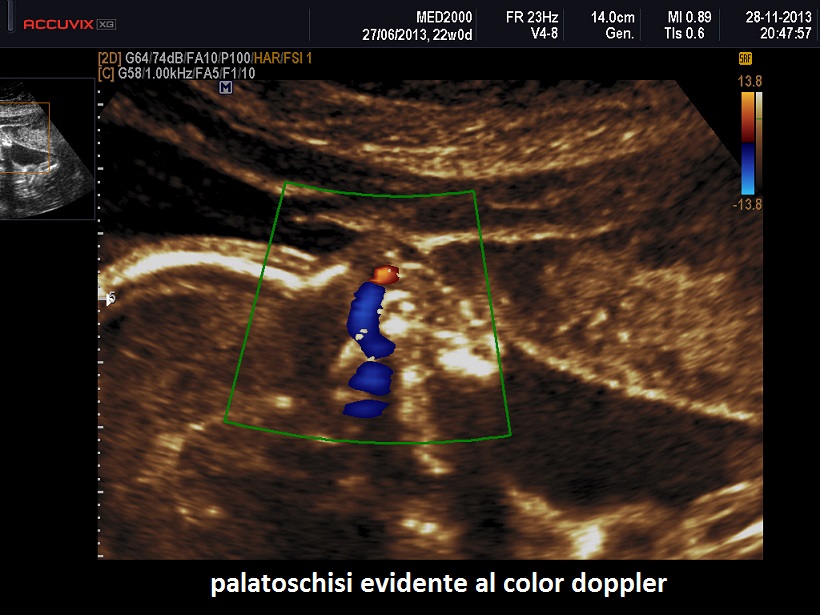

Possono essere presenti: idrope, cardioaptie congenite, labiopalatoschisi, oligoamnios, anomalie genito-urinarie, anomalie gastro-intestinali, anomalie del SNC.

Sono frequenti le cardiopatie congenite e la labiopalatoschisi mediana. La polidattilia è preassiale e interessa mani e piedi. Può essere presente oloprosencefalia e genitali ambigui.

Sono presenti labiopalatoschisi, anomalie genitourinarie ed anomalie gastrointestinali. Può essere presente idrope ed ascite.

4)    I tipi II e IV  presentano labiopalatoschisi.